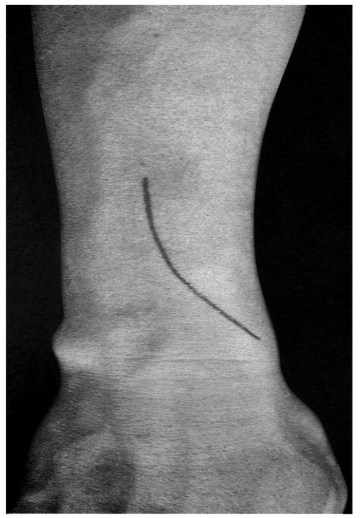

术前拍腕关节正、侧位X线片,腕关节冠状位、矢状位和水平位CT(图2-2)此患者骨缺损和无法闭合复位的骨片均在背侧,宜采用背侧入路,复位,植骨,固定。取患肢前臂远端桡背侧纵切口(图2-3)从伸拇长肌腱和桡侧伸腕长、短肌之间进入,注意保护血管神经和肌腱,显露清理折端骨缺损区域和背侧移位的骨片(图2-4复位,植骨,外固定架超关节固定(图2-5、图2-6)。术中透视骨折复位固定满意(图2-7),术后拍X线片证实(图2-8)。此手术的优点在于避免了局部存在内固定物的刺激,避免二期切开取出固定物所致的再次损伤。

图2-3 切口起自桡骨茎突,向上沿桡骨后缘并略偏向尺侧